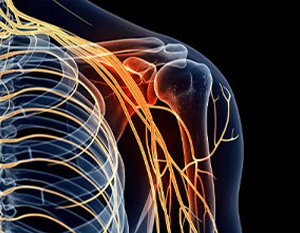

Neuropathy Symptoms & Conditions

Tired of Peripheral Neuropathy?

You don't have to live with the tingling, numbness or stabbing,

burning sensations that come along with neuropathy! At Hifai Chiropractic, our personalized treatments can

help relieve your condition.